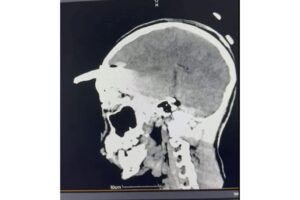

El Instituto Mexicano del Seguro Social (IMSS) en Yucatán logró un hecho médico sin precedentes al retirar, mediante una compleja cirugía, una coa (herramienta para la agricultura) de aproximadamente 30 centímetros incrustada en el cráneo de un adolescente de 15 años, procedimiento que permitió salvarle la vida.

El 2 de noviembre pasado, Yael fue trasladado desde el municipio de Acanceh al Hospital General Regional (HGR) No. 12 del IMSS en Mérida, donde la directora, doctora Claudia González Ramírez, y un equipo de especialistas ya se encontraban preparados para recibirlo y atender la emergencia. Tras confirmarse un traumatismo craneoencefálico severo, se realizaron estudios inmediatos que determinaron la profundidad y ubicación del objeto.

Los estudios de imagen permitieron ubicar con precisión el objeto, mientras que el menor recibía tratamiento con antibióticos de amplio espectro para prevenir infecciones asociadas con el instrumento metálico.

Después de un análisis minucioso y una planeación quirúrgica, el doctor Ornelas González dirigió un procedimiento de cuatro horas que permitió retirar exitosamente el machete curvo sin afectar tejido cerebral, en una intervención que confirmó la pericia y capacidad del equipo médico.